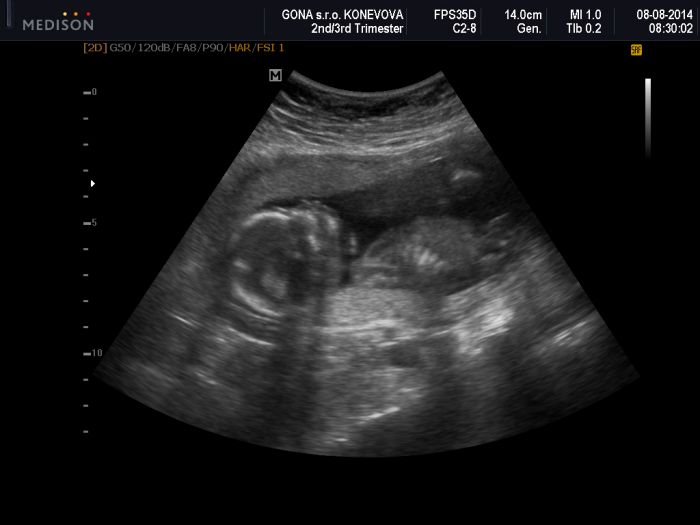

Tak ještě sem dám fotku našeho miminka-jak ukazuje dlouhý nos. To dítě bude mít smysl pro humor

Ahoj holky,tak se hlásím z včerejšího velkýho utz,dneska jsme 21+0 všechno v pořádku,tak teď už si to budeme jen užívat :-) Teď vyřázíme ke švagrové,ta čeká prcka v září,tak budeme mít v rodině veselo :-) Přikládám vám foto :-) Jinak Gilmorovi děvčata taky můžu,ale teď co jsem doma tak čumím v televizi snad na všechno :-)